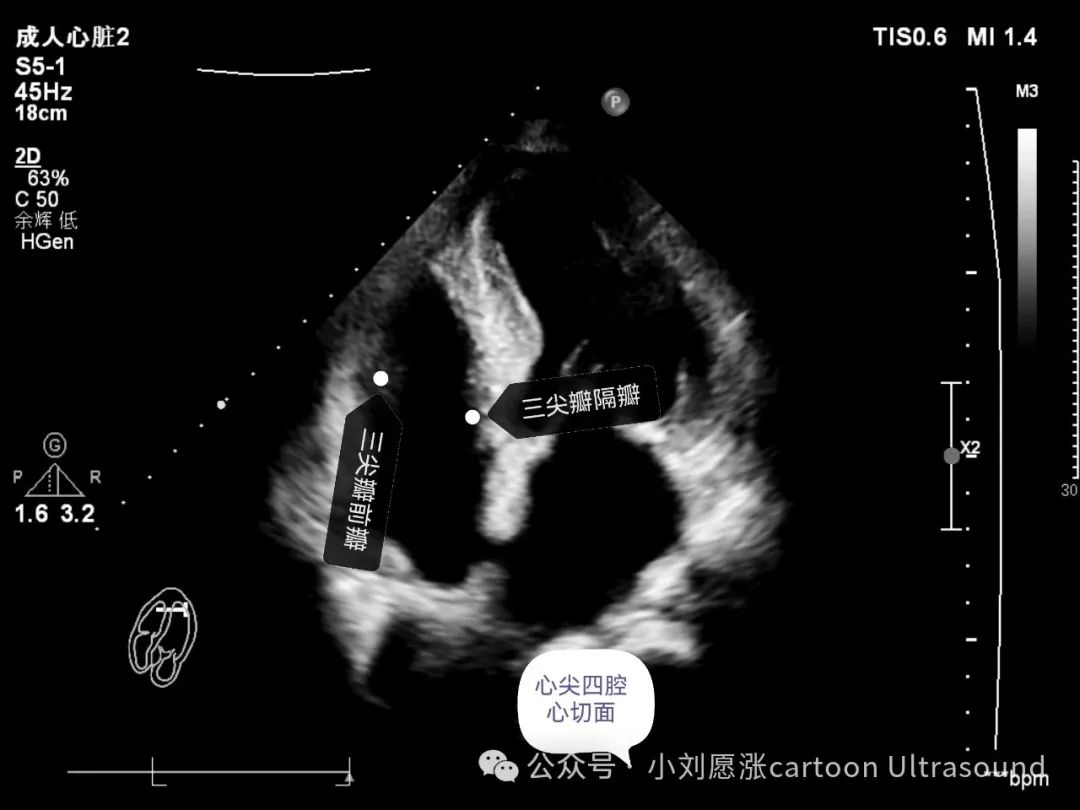

三尖瓣:3个瓣叶,前瓣、后瓣、隔瓣,后瓣只能右室流入道切面观察。